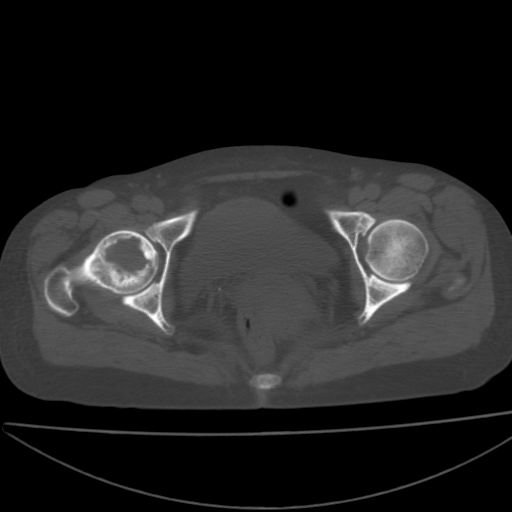

以下是引用xiaoniu在2008-9-6 8:22:00的发言:[br]右侧股骨颈囊性低密度,囊壁边缘硬化,中年妇女,首先考虑:骨囊肿。其次考虑动脉瘤样骨囊肿。[br][br][br][本贴已被 xiaoniu 于 2008-9-6 9:04:54 修改过]